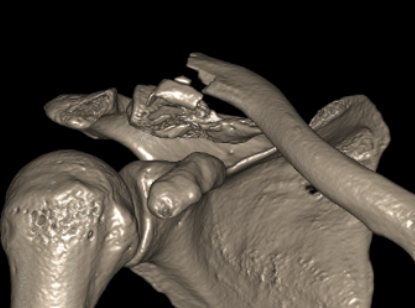

Neer Classification

Fracture lateral to the CC ligaments Non displaced

|

Fracture medial to the CC ligaments CCL ligaments attached to lateral fragment Medial fragment displaced superiorly |

Between conoid and trapezoid Conoid disrupted Trapezoid remains attached to the lateral fragment |

Lateral to CC ligaments Intra-articular extension Stable |

Periosteal sleeve disruption Pediatric Medial fragment displaced |

Comminuted Type II Medial fragment displaced |

Type I

Type II

Type V